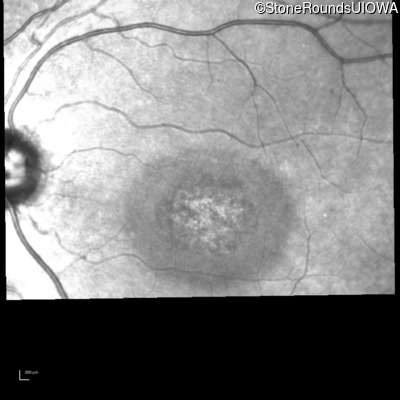

Infrared Fundus Photograph - Right - 20/200

Exemplar